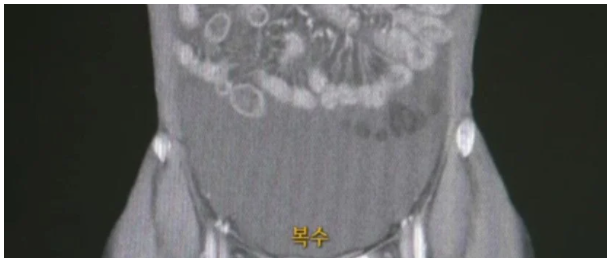

술꾼들 주목! 술 진짜 적당히 마셔야 하는 이유